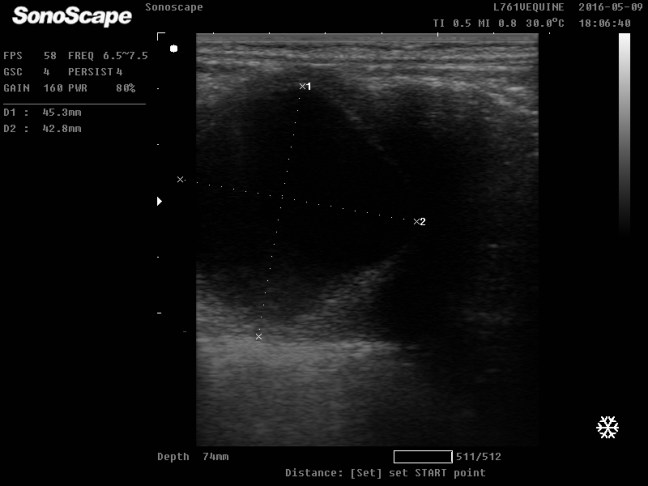

Ocena momentu owulacji u klaczy - Kontrola źrebności klaczy badaniem USG- dzięki zastosowaniu ultrasonografii ciążę możemy potwierdzić już w 9 dniu po owulacji, jednak największą wartość diagnostyczną mają badania przeprowadzone w 21 dniu po owulacji.